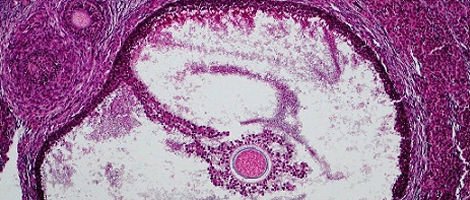

Durante a fase pré-ovulação do ciclo o aumento de FSH faz com que vários desses folículos comecem a crescer e migrem até a superfície do ovário. O crescimento dos folículos produz o aumento de uma outra hormona chamada estradiol cuja função é bloquear a produção de FSH pela hipófise para que apenas um dos folículos complete o seu desenvolvimento total. O crescimento dos restantes folículos é bloqueado. O folículo dominante é chamado de folículo de Graaf e produz outras hormonas que actuam sobre o útero, fazendo com que o endométrio prolifere e facilitando a posterior implantação do embrião.

Até metade do ciclo (14º-15º dia) a hipófise produz uma subida dos níveis de LH que provoca a ruptura do folículo de Graaf, permitindo que o óvulo maduro saia do ovário em direcção as trompas. Este processo é denominado de ovulação.